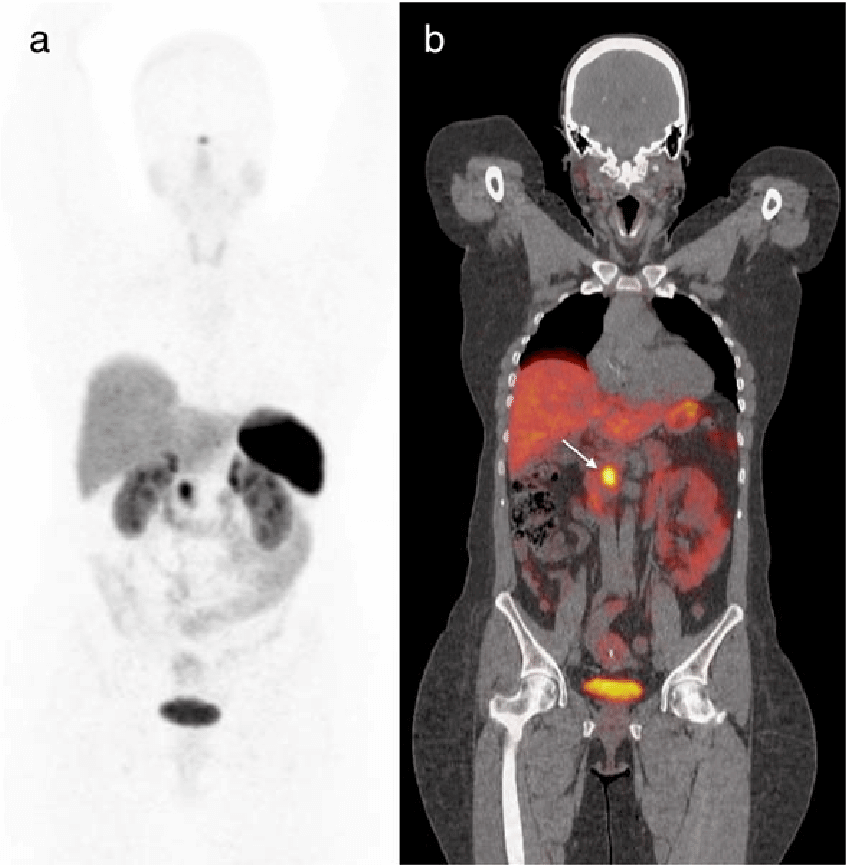

A DOTA PET scan is primarily used to evaluate neuroendocrine tumors and related conditions that express somatostatin receptors. It helps in identifying the primary tumor site, detecting metastasis, and assessing disease extent with high accuracy.

This scan is commonly recommended for conditions such as gastroenteropancreatic neuroendocrine tumors, bronchial carcinoids, and other receptor-positive neuroendocrine malignancies, where targeted imaging is essential for clinical decision-making.

A DOTA PET scan works by using a radiotracer that binds to somatostatin receptors present on certain tumor cells. After the tracer is administered, it circulates through the body and attaches to receptor-positive tissues, allowing precise imaging of tumor activity.

The PET-CT system then captures detailed images that help doctors assess tumor location, spread, and receptor expression, supporting accurate diagnosis and treatment planning.